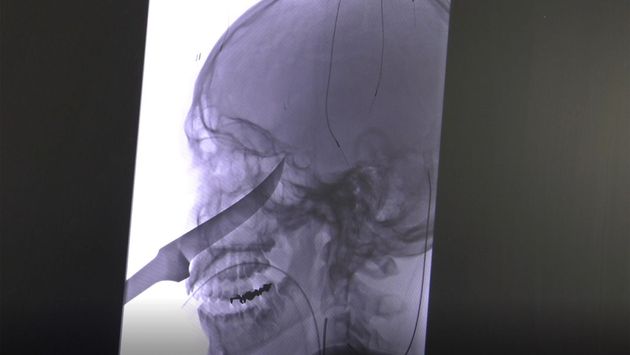

25cm 짜리 칼이 얼굴에 박힌 소년이 기적적으로 살아났다

ⓒUniversity of Kansas Health

엘리는 칼을 갖고 놀다가 넘어졌다. 그때 칼이 얼굴에 박힌 것이다. 칼은 얼굴을 관통해 두개골에 박혔고, 칼날 끝은 경동맥 바로 옆을 스쳐지나갔다.

엘리는 앰뷸런스를 타고 바로 아동병원으로 이송됐다. 그곳 의사들은 칼이 경동맥 옆에 위치한 상태라는 사실을 파악했다. 자칫 수술과정에서 뇌졸중이 발생할 수 있는 상황이었다. 엘리는 바로 캔자스 보건 시스템 대학 병원으로 옮겨졌다. 다행히 엘리는 늦지 않게 수술을 받을 수 있었다.

수술을 집도한 코지 에버솔 박사는 ”칼이 아슬아슬한 위치에 있었다”며 ”조금이라도 힘이 더 가해졌다면 살아나지 못했을 것”이라고 말했다.